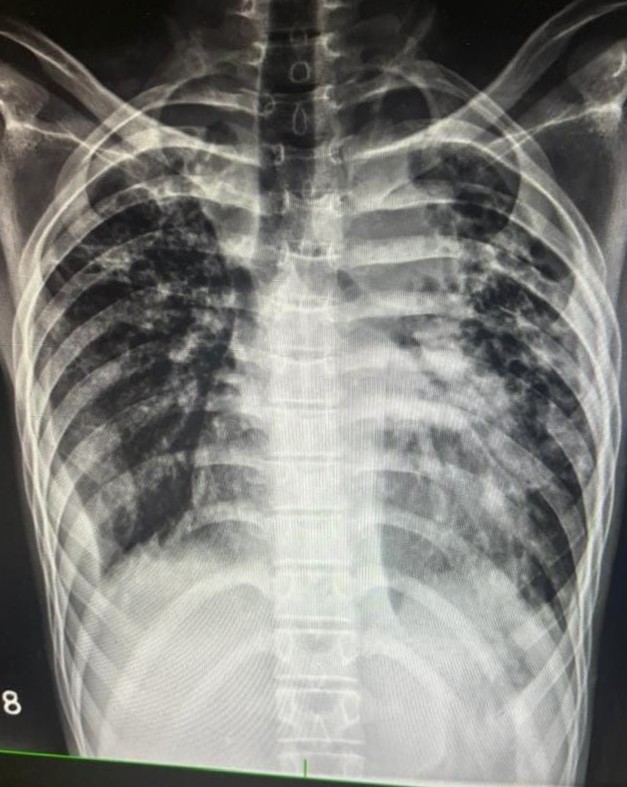

| 4 | IGGMC, Nagpur, Nagpur | P2 | 29-4468 | Moh. Salehuddin | Consent taken on Paper | 68 Yrs. |

Provisional Diag : Miliary TB?

Final Diag : Miliary TB |

TB Case (Confirmed) | Bilateral Infiltrate Query Miliary | Abnormality visible on x-ray |

View |

|||